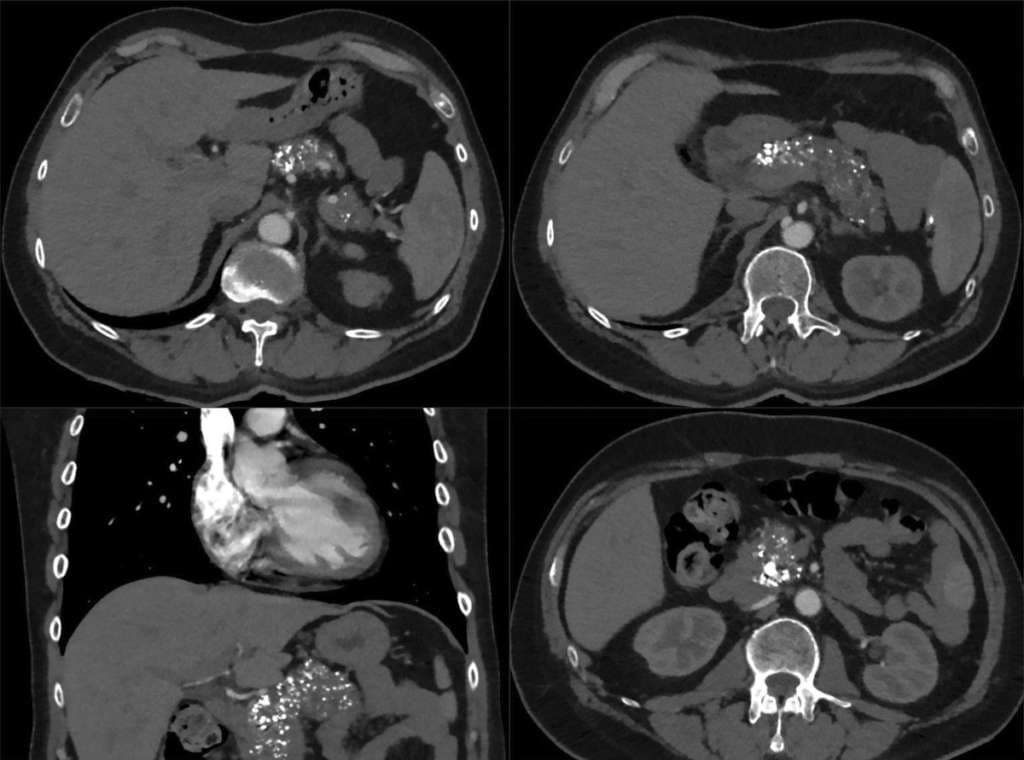

Der Verdacht auf eine chronische Pankreatitis lässt sich anhand multipler Verkalkungen der Pankreasgänge bestätigen, die in der kontrastmittelgestützten CT sofort ins Auge fallen.

Eine chronische Pankreatitis entwickelt sich in der Regel aus rezidivierenden akuten Pankreatitiden, typischerweise innerhalb von drei bis fünf Jahren nach der initialen Episode. In der Bildgebung zeigen sich Kalzifikationen der Pankreasgänge, duktale Dilatationen und/oder eine parenchymale Atrophie. Die Risikofaktoren umfassen Alkohol (bei 42–77% der Betroffenen), Rauchen (> 60%) und genetische Mutationen (10%).